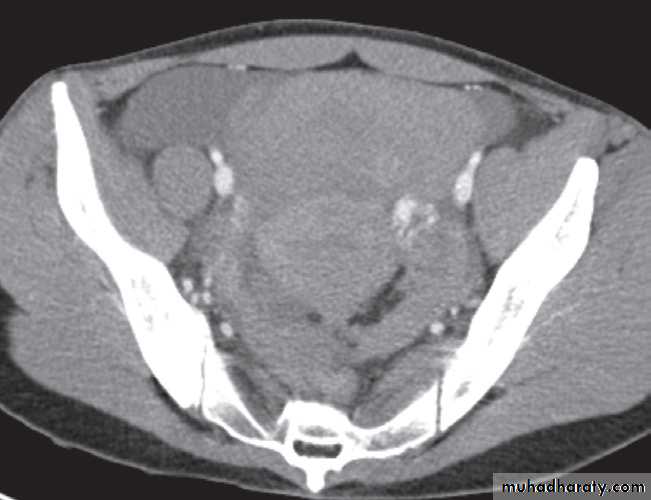

Ectopic pregnancy generally presents with sudden pain due to rupture of the ectopically placed gestational sac and should be managed as a medical emergency.Sonographically, it is identified as an adnexal mass having both solid and cystic characteristics, and occasionally a fetus can be seen within it .

On CT, high density free fluid may be seen in the pouch of Douglas from haemorrhage .

The DDX:

-Pelvic inflammatory disease.-Rupture of adnexal cysts .

-Various neoplasms .

In clinical practice, if the pregnancy test is positive and no intrauterine gestation can be identified, the obstetrician may assume that there is an ectopic pregnancy.